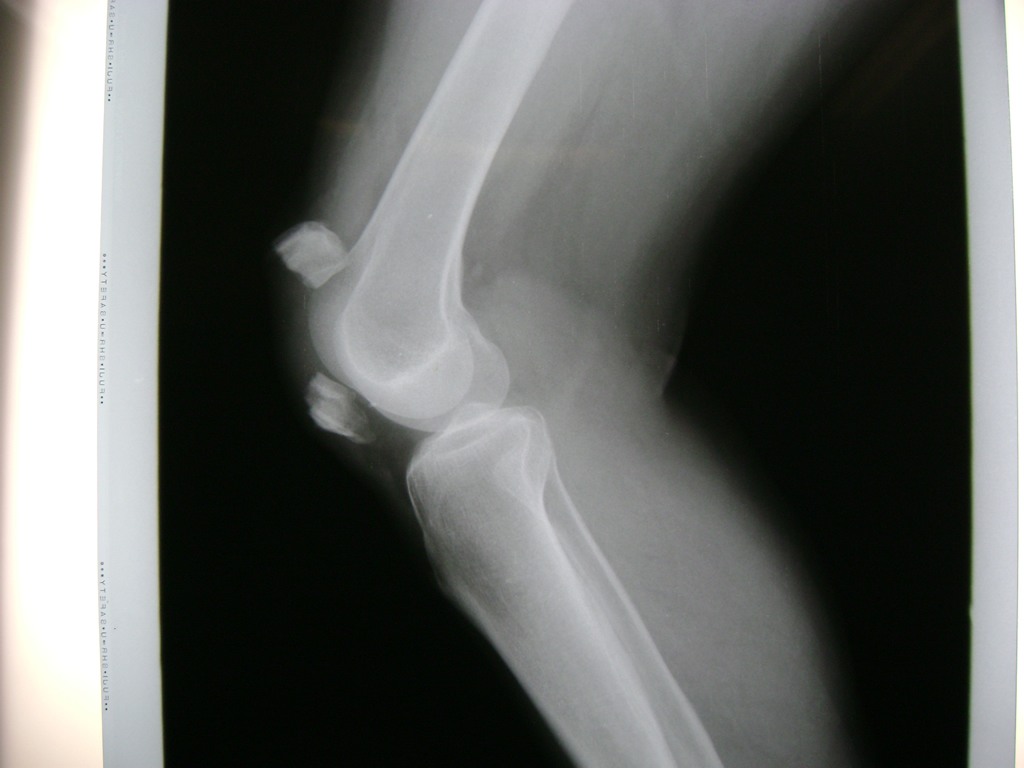

Húmero - Rodilla

La artroscopia de rodilla es un cirugía en el cual la estructura interna de la articulación es examinada ya sea para realizar un diagnostico o para realizar un tratamiento, este procedimiento se realiza utilizando un instrumento parecido a un pequeño tubo llamado artroscopio.